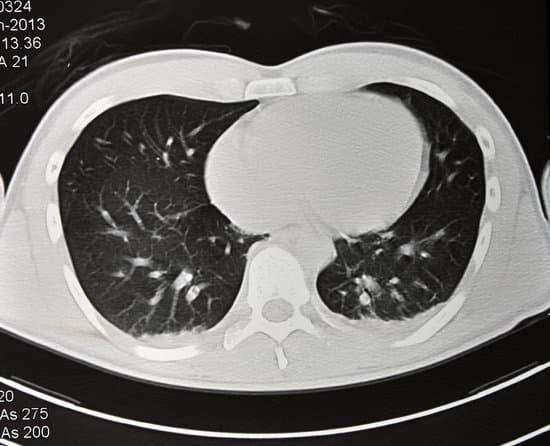

폐 CT(Computed Tomography) 검사는 폐와 기관지를 포함한 흉부 장기의 상태를 보다 정밀하게 확인할 수 있는 영상 촬영 기법입니다. X-ray 촬영보다 더 세밀한 영상을 제공하기 때문에 폐암, 폐렴, 폐섬유증, 결핵 등의 다양한 폐 질환을 진단하는 데 매우 효과적입니다. 특히 저선량 폐 CT는 폐암 조기 발견에 중요한 역할을 하며, 흡연자와 고위험군에게 권장되는 검사입니다.

폐의 염증성 질환인 폐렴은 X-ray보다 CT를 통해 더 명확하게 염증의 범위와 정확한 위치를 파악할 수 있습니다.

정밀도: X-ray는 폐의 전체적인 구조를 단순하게 촬영하는 반면, CT는 단층 촬영을 통해 폐 내부를 여러 각도에서 세밀하게 관찰할 수 있습니다.

조기 진단: CT는 폐암, 결절 등의 작은 병변을 조기에 발견할 수 있지만, X-ray는 이러한 병변을 발견하기 어려울 수 있습니다.